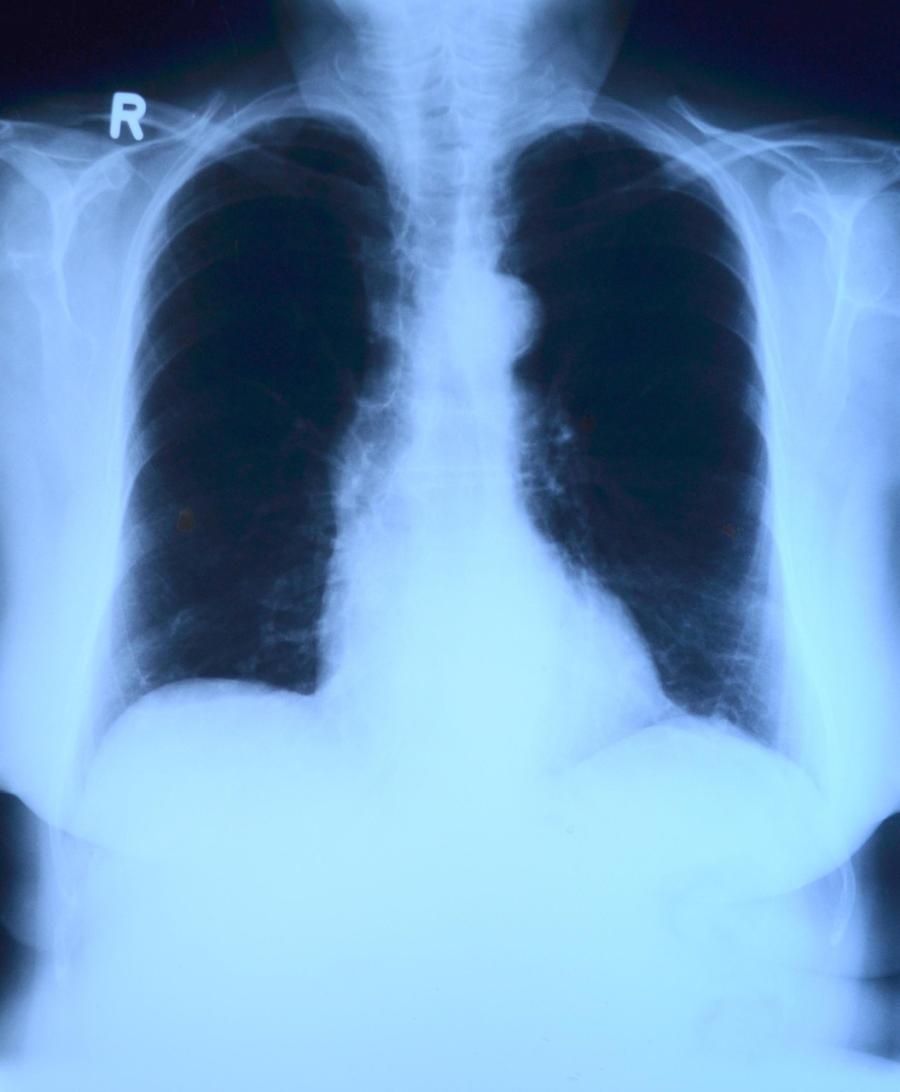

Upala pluća (pneumonija) je ozbiljna infekcija koja zahvata plućno tkivo i može biti uzrokovana bakterijama, virusima ili, ređe, gljivicama.